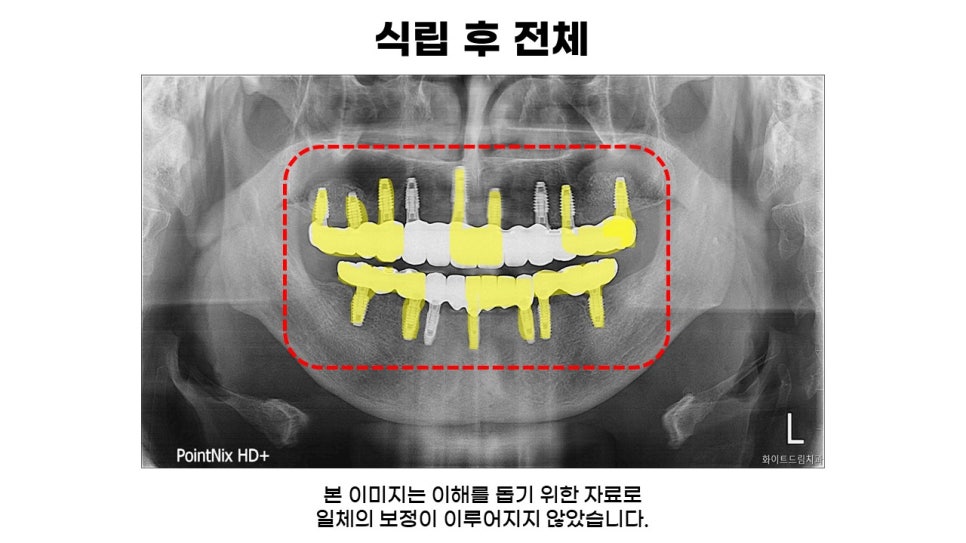

상악동 거상술과 치조골 이식을 통해 보철식립 해드린 중간결과 모습과 전체 인상채득 후 보철이 완성된 모습인데요.

다수의 임플란트를 연결해서 보철물을 제작하는 등 파절과 재식립을 예방하기 위해 힘이 가해지는 각도와 위치를 고려하여 적절한 길이로 식립해 드린 모습입니다.

마지막으로, 상악 좌, 우측 상악동 거상술과 상, 하악 치조골 이식을 동반한 임플란트 식립 후 최종 결과물 입니다.

상악과 하악 모두 자연치와 유사하게 식립되어졌으며, 9, 7개 임플란트 식립 후 나머지 4, 7개 치아는 치료기간을 단축해드리고 비용 부담을 줄여드리기 위해 브릿지를 사용해드렸습니다.